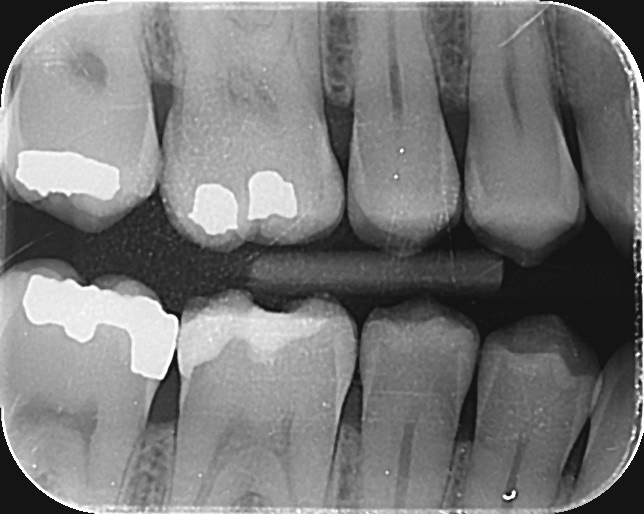

9. Which surfaces shows root caries?

10: What is the caries level on occlusal of the tooth # 2.7?

11. What is the caries level of the distal surface of the toot # 3.5?

12. Which surface shows Cervical burn out?